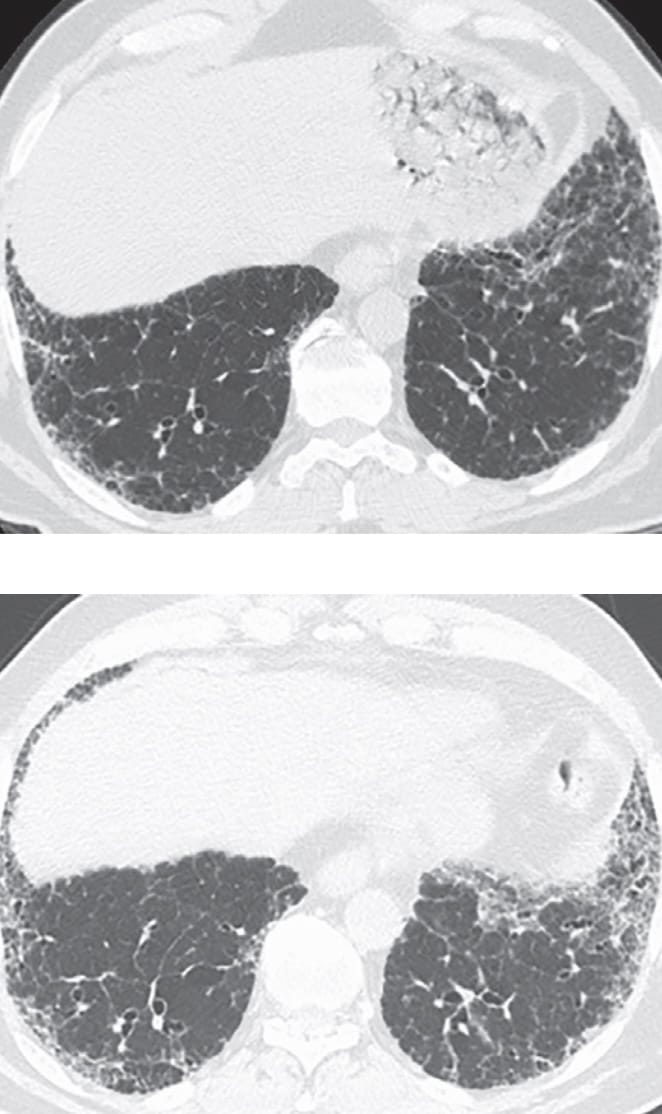

- Usual Interstitial Pneumonia

- Fibrotic Hypersensitivity Pneumonitis